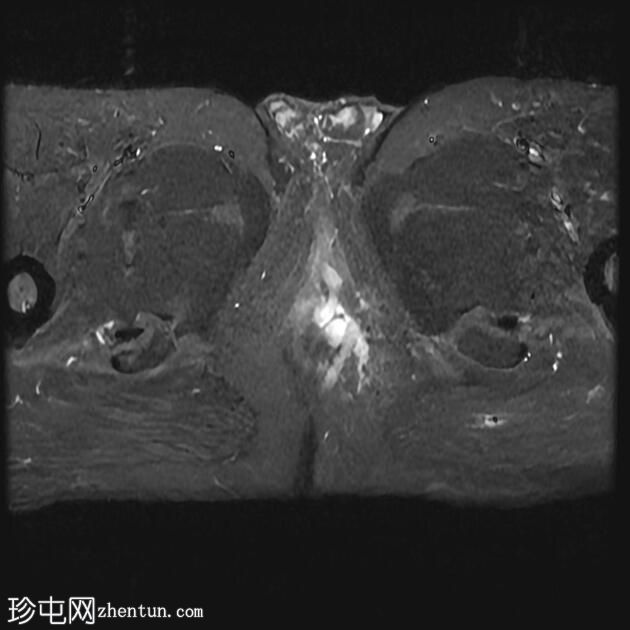

MRI

轴向位

T2

轴向位T2

脂肪饱和度

T1

轴向位T1

冠状位T1

冠状位

冠状位T2

C+脂肪饱和度

一条68毫米厚的强化通道始于左侧肛周区域,向上穿过肛门内外括约肌,在2点钟方向开口于肛管。

无脓肿形成。

MRI成像特征与所述左侧经括约肌肛周瘘相符。